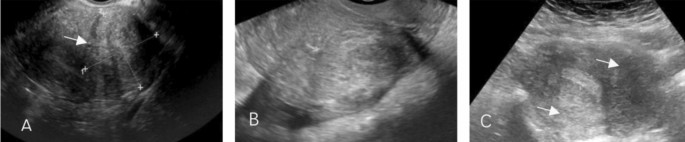

Surgical data were also collected from the laparoscopic files. Each patient’s revised American Society for Reproductive Medicine (rASRM)9 classification based on the revised American Fertility Society (rAFS) Score, and EFI (Endometriosis Fertility Index) score10 were collected according to the patients’ surgical records and infertility history. Post-surgical symptoms and pregnancy outcomes were collected from follow-up interviews with the patients. Adenomyosis diagnosis1 was established through a combination of physical examination, imaging, and pathology. A physical examination and two-dimensional color Dopper transvaginal ultrasound (2D-TVS) (Fig. 1) were performed the day before surgery for clinical diagnosis, and the diagnosis was further verified by histology (adenomyosis resection or biopsy) or MRI. For the purposes of the present study, the patients were divided into three groups according to the location of adenomyosis (anterior, posterior, both posterior and anterior) identified by ultrasound.

Two-dimensional transvaginal ultrasound images of adenomyosis. (A) with anterior adenomyosis; (B) with posterior adenomyosis; (C) with both anterior and posterior adenomyosis.